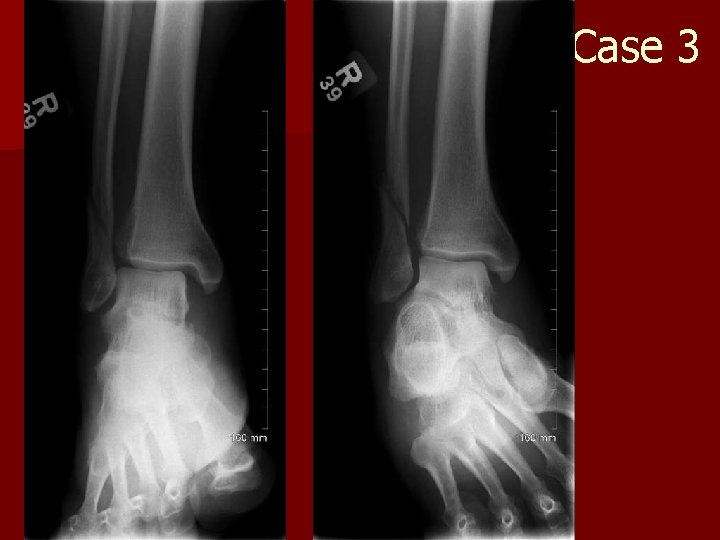

Case 3 n 69 y. o. who fell

Case 3

Case 3 n What are the 3 radiographs that are obtained with an ankle series? – AP, lateral, ankle mortice view n How is the ankle mortice view obtained? – Internal rotation 15 degrees n What does the ankle mortice view tell you clinically? – Ankle joint stability!

Ankle and foot anatomy Proximal phalynx Sesamoid metatarsal 3 rd cuneiform Cuboid 2 nd cuneiform Talus Calcaneus 1 st cuneiform Navicular